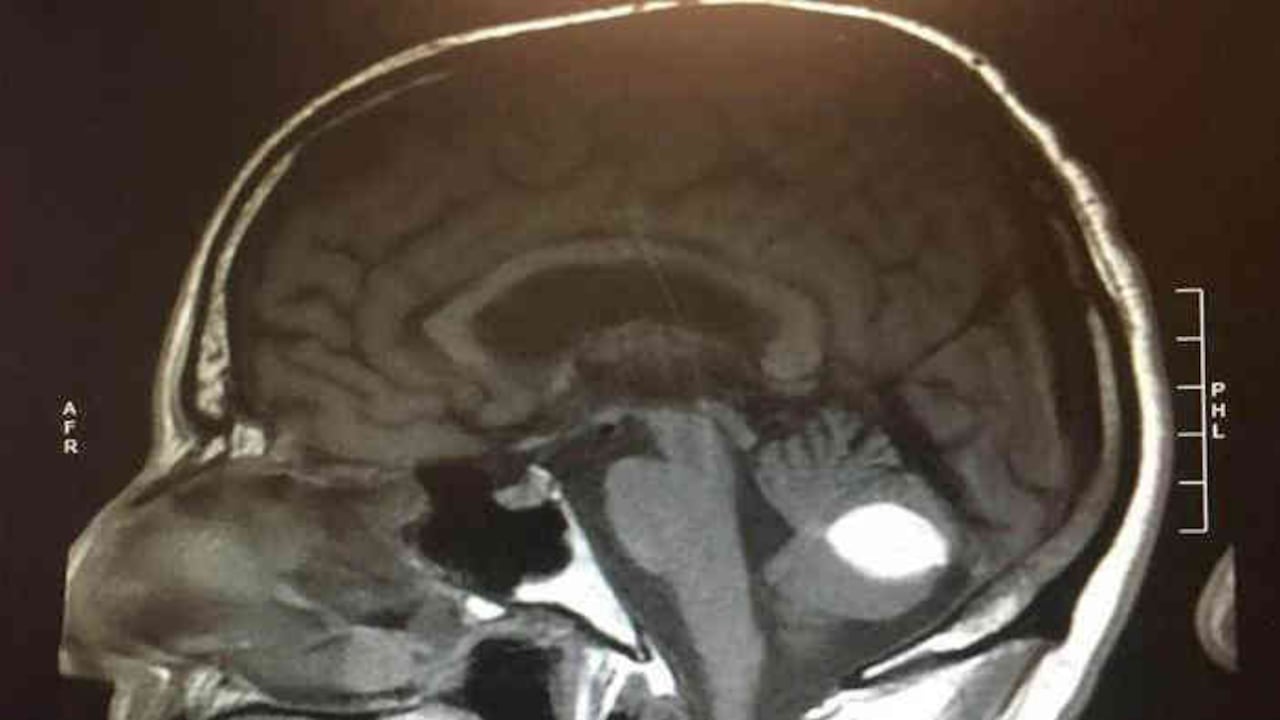

Después de visitar al médico y de realizarse varios estudios, un neurocirujano le diagnosticó que tenía una hemorragia cerebral mientras que radiólogos consideraron que se podía tratar de un tumor en el cerebro.

Inesperadamente Woods se empezó a sentir mejor y el día antes de la cirugía se sometió a nuevas pruebas en las que no se encontró el tumor que inicialmente le habían dictaminado.